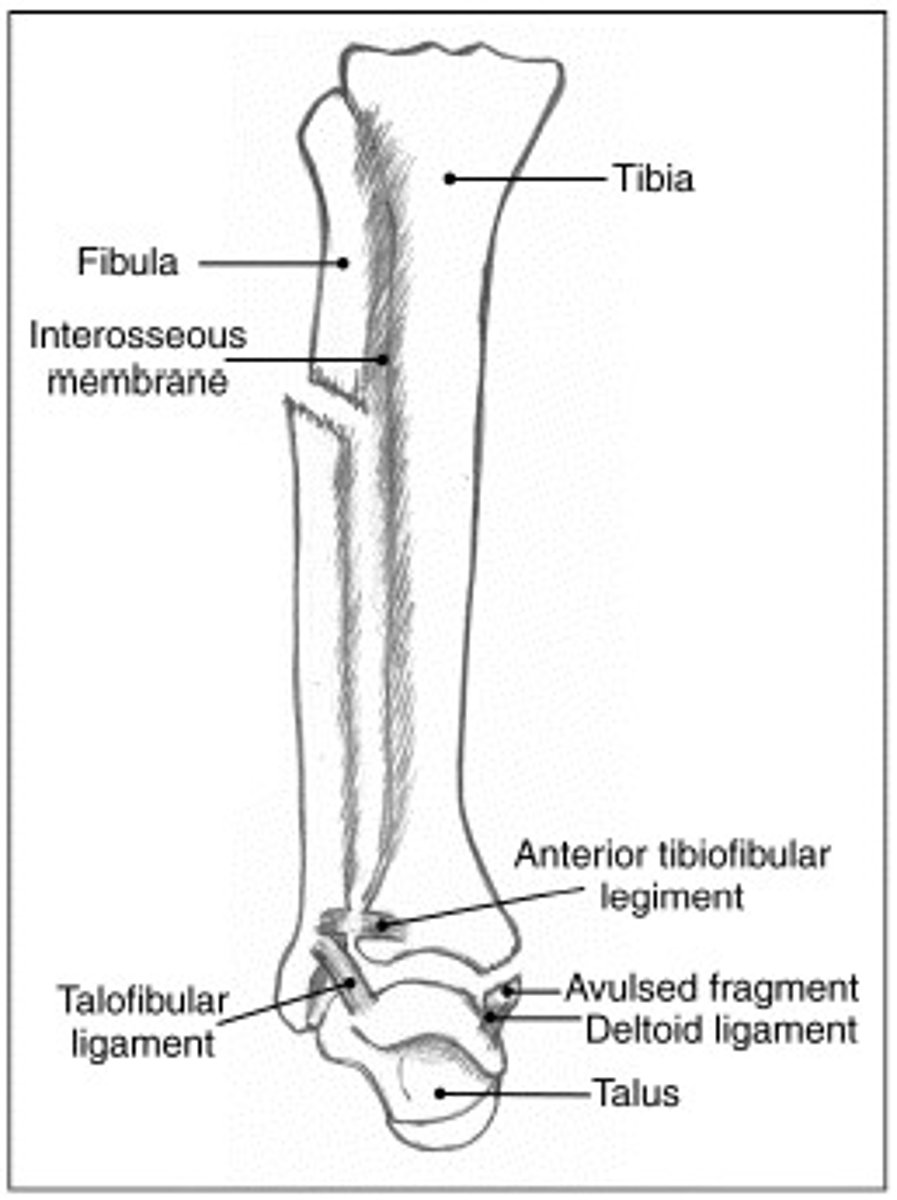

Maissoneuve Fracture

∙Fibular neck fracture.

∙Proximal fibular fracture due to external rotation.

∙Energy of rotation transfers through the interosseous ligament and exits at proximal fibula.

∙Requires Syndesmotic fixation.

What views should you get to rule out a maissoneuve fracture?

-Fibula

-Tibia

-Ankle

What do we see transverse medial malleolar fractures with in terms of mechanism of injury?

Eversion ankle injuries. Then with lateral malleolar (more common) we see with inversion ankle injuries.